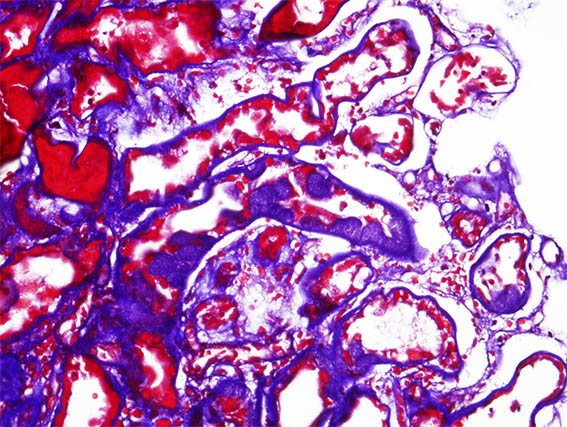

The patient is a 41-year-old woman with diabetes, who developed abrupt nephrotic syndrome, for which a kidney biopsy was performed. The biopsy shows advanced diabetic nephropathy without superimposed GN.

There is an area of tubular lesions as in the images:

Figure 2. Masson's trichrome stain, X400.